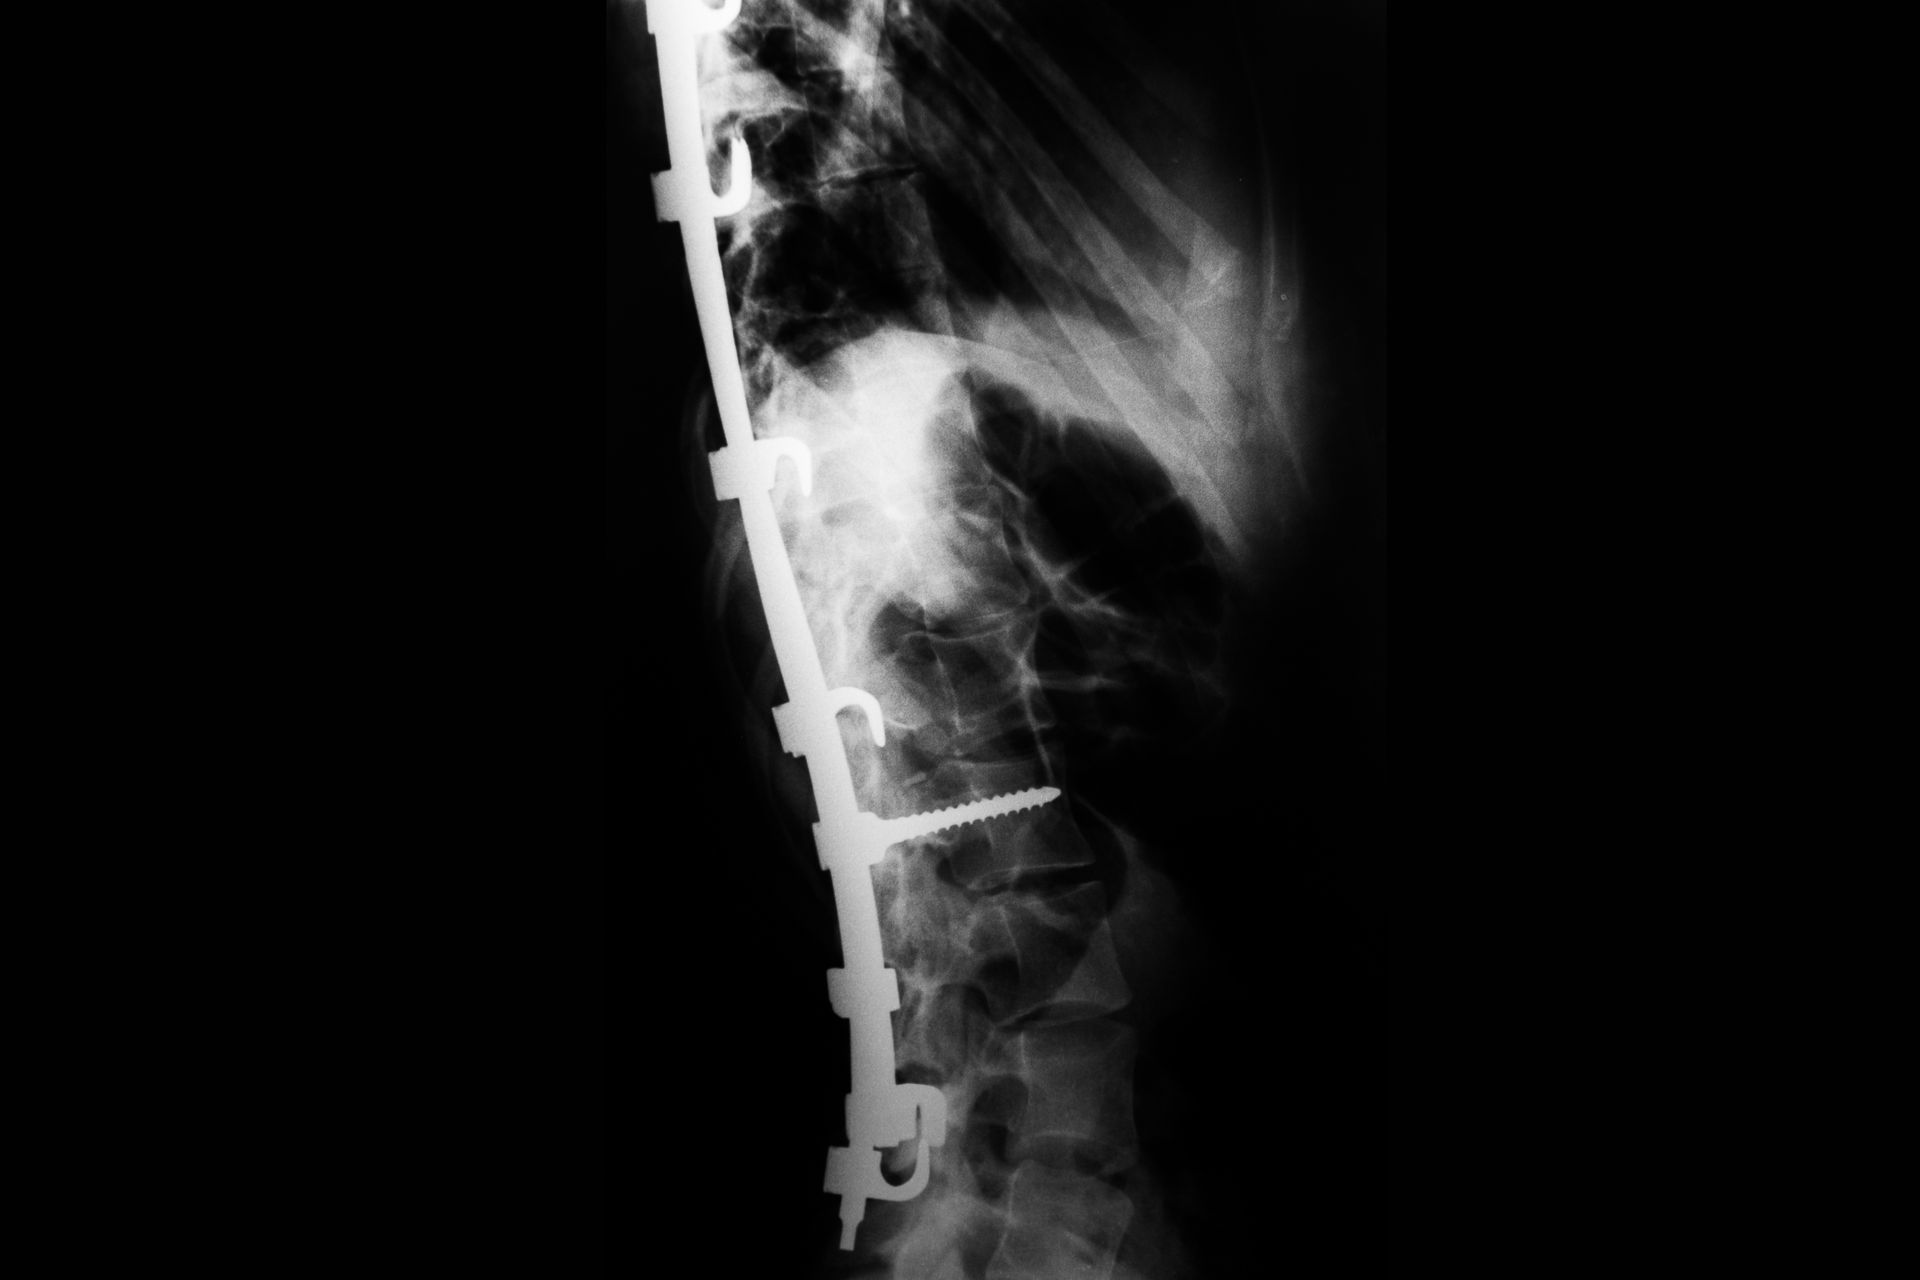

Aos 18 anos mais uma cicatriz, essa com o fantasma que eu poderia não sobreviver, uma cicatriz por toda extensão das minhas costas, porém mais uma batalha vencida.